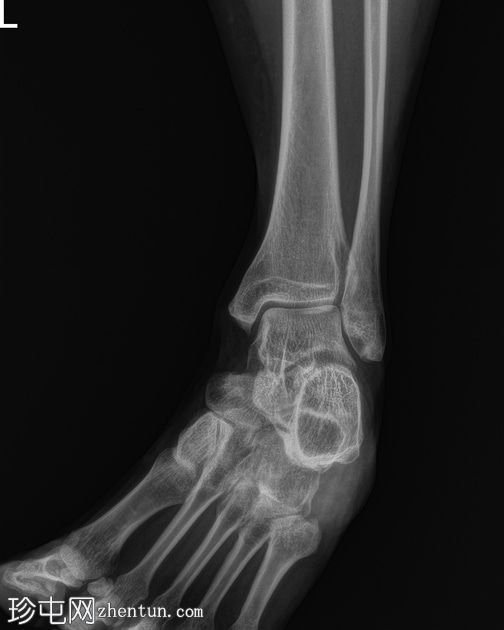

X线片

斜位片

双侧跟骨密度增高,可见跟骨骨骺碎片,提示跟骨骨骺炎,又称塞弗氏病。

塞弗氏病,又称跟骨骨骺炎,是生长发育期儿童足跟(或跟骨)生长板后方的炎症。

该病被认为是由足跟反复受力引起的。这种疾病良性且常见,通常在生长板闭合后或活动量减少时缓解。